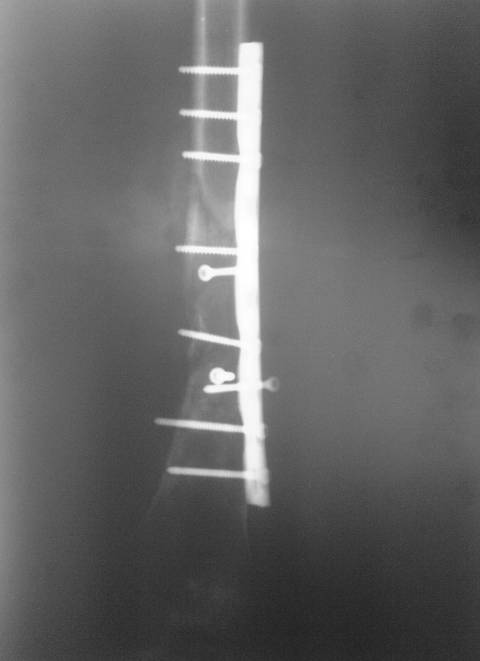

В мае 2007 года оперирована в Уральском НИИТО г. Екатеринбурга. Выполнено: полузакрытое удаление пластины и винтов, IM блокируемый остеосинтез.

На сегодняшний момент (2 месяца после операции). Больная передвигается при помощи трости из-за чувства неуверенности и ощущения онемения в подколенной ямке. В квартире передвигается без дополнительной опоры. Снимки в аттаче.

Возникли вопросы по дальнейшей тактике ведения такой больной:

1. Удалять ли статический винт? Сроки? Способ?

2. Причины и возможные методы лечения индуративного отека н/3 бедра?